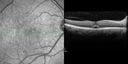

75 year old man with 2 weeks of vision loss in both eyes. He has serous retinal detachments and choroidal effusions more in the left eye than the right eye. He has been getting every 3 week testosterone shots for 1.5 years. He was at a weight loss clinic from 6 to 3 months ago and had Lipo-B shots and lost 35 lbs. He also takes daily Cialis on his doctors recommendations for low testosterone. He is otherwise in good health. Vision is 20/40 right eye, 20/50 left eye. The images show the choroidal effusion with choroidal thickening. This spontaneously resolved without altering his systemic testosterone or cialis therapy over the course of about 4 months

Choroidal Effusions and Serous retinal detachment with Systemic Testosterone and Cialis in 75 year old Man513 viewsOCT line scans at different visits showing the improvement of the left eye with decreasing choroidal thickness and subretinal fluid. No treatment was given.00000